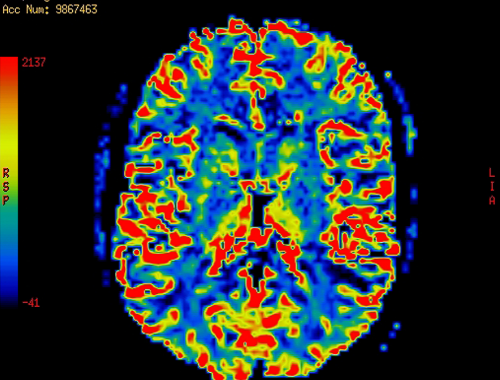

Table of differences between narcolepsy brain and normal brain